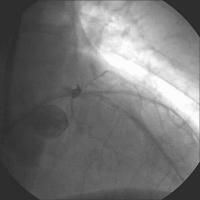

Linke Koronararterie RAO/Kranialprojektion

Abbildung 1: 50 % Ostiumstenose Hauptstamm, Bifurkationsstenose LAD – 1. diagonaler Ast (echte Bifurkationsstenose Typ IV ICPS- Klassifikation ), Y-konfigurierter Abgang des Seitenastes. Kollateralen zur verschlossenen RKA.

Keywords: BifurkationsstenoseKardiologieKoronarangiographieOstiumstenose